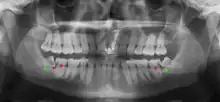

If the tooth cannot be assessed with clinical exam alone, the diagnosis is made using either a panoramic radiograph or cone-beam CT. Where unerupted wisdom teeth still have eruption potential several predictors are used to determine the chance of the teeth becoming impacted. The ratio of space between the tooth crown length and the amount of space available, the angle of the teeth compared to the other teeth are the two most commonly used predictors, with the space ratio being the most accurate. Despite the capacity for movement into early adulthood, the likelihood that the tooth will become impacted can be predicted when the ratio of space available to the length of the crown of the tooth is under 1.[5]: 141

Impacted wisdom teeth are classified by their direction of impaction, their depth compared to the biting surface of adjacent teeth and the amount of the tooth's crown that extends through gum tissue or bone. Impacted wisdom teeth can also be classified by the presence or absence of symptoms and disease. Screening for the presence of wisdom teeth often begins in late adolescence when a partially developed tooth may become impacted. Screening commonly includes a clinical examination as well as x-rays such as panoramic radiographs.

There is no standard to screen for wisdom teeth. It has been suggested, absent evidence to support routinely retaining or removing wisdom teeth, that evaluation with panoramic radiograph, starting between the ages of 16 and 25 be completed every 3 years. Once there is the possibility of the teeth developing disease, then a discussion about the operative risks versus long-term risk of retention with an oral and maxillofacial surgeon or other clinician trained to evaluate wisdom teeth is recommended. These recommendations are based on expert opinion level evidence.[19] Screening at a younger age may be required if the second molars (the "12-year molars") fail to erupt as ectopic positioning of the wisdom teeth can prevent their eruption. Radiographs can be avoided if the majority of the tooth is visible in the mouth.